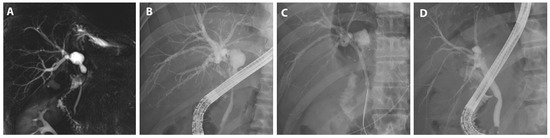

Despite the potential of non-surgical BBS emanating from diverse etiologies including primary sclerosing cholangitis and IgG4-related cholangiopathy, their representation in our study was scant. Hence, we consolidated non-surgical BBS cases into a singular category. For the patient presented in this study, only benign fibrotic tissue was confirmed histologically, and there were no IgG4 or other pathological findings, so the patient is being followed up on an outpatient basis after treatment of the stricture (Figure 5).

Figure 5.

FCSEMS treatment of BBS. A case of BBS diagnosed by histological findings and treated with FCSEMSs is presented. (A) Cholangiography with PTBD confirmed left biliary stricture. (B) Percutaneous transhepatic cholangioscopy was used for histological examination. (C) Histological examination was performed on the area of biliary stricture. (D) An FCSEMS (10 mm in diameter, 4 cm in length; KAFFES) was inserted into the BBS. (E) The FCSEMS was successfully deployed. (F) After 12 months of FCSEMS use, including three replacements, the stent was removed, and the procedure was terminated after confirming that the BBS had resolved.